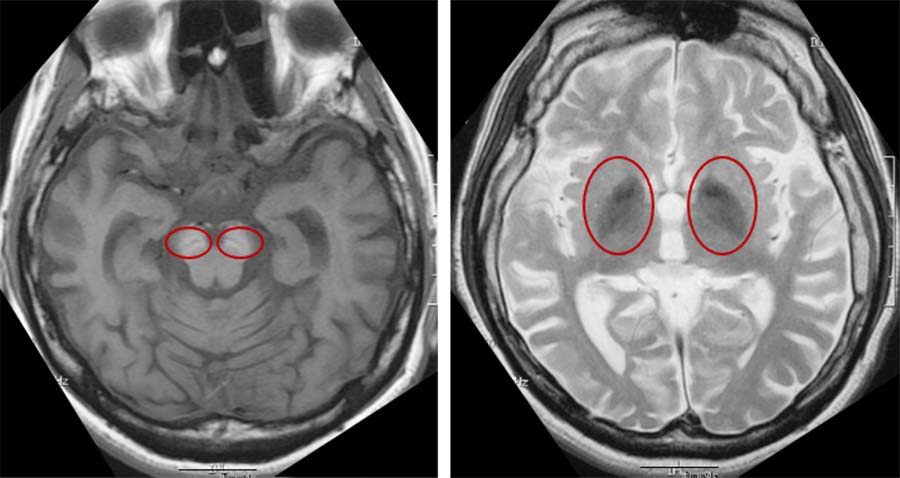

大脳皮質下に嚢胞性病変が集簇してみられるMVNTとは?MRI画像所見のポイント

大脳皮質下に嚢胞性病変が集簇してみられるMVNTとは?MRI画像所見のポイント

大脳皮質下に嚢胞性病変が集簇してみられるMVNTとは?MRI画像所見のポイント,

大脳皮質下に嚢胞性病変が集簇してみられるMVNTとは?MRI画像所見のポイント, SENDA/BPAN | オートファジー病(SENDA/BPAN・Vici症候群),